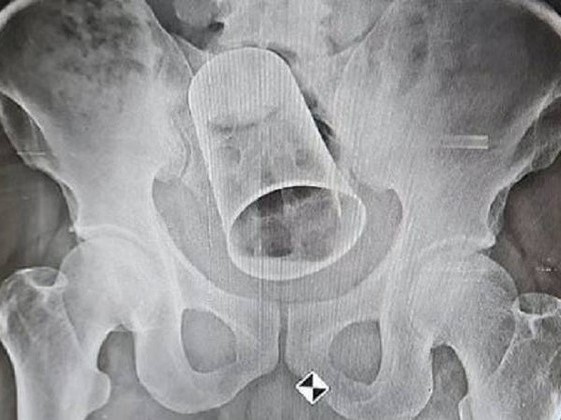

Bị bạn 'đùa nghịch' dùng vòi hơi xịt vào hậu môn, nam thanh niên vỡ đại tràng

Nam bệnh nhân 18 tuổi được đưa đến bệnh viện cấp cứu trong tình trạng đau bụng dữ dội, co cứng khắp vùng bụng vì vỡ đại tràng và trực tràng

Mắc kẹt dị vật khủng trong hậu môn, thầy phán 'bị yểm bùa trong bụng'

Các bác sĩ nhận định, dị vật này do bệnh nhân hoặc ai đó nhét vào hậu môn chứ không có chuyện bệnh nhân "bị thư, yểm bùa ngải" như bệnh nhân khai lúc mới vào viện.